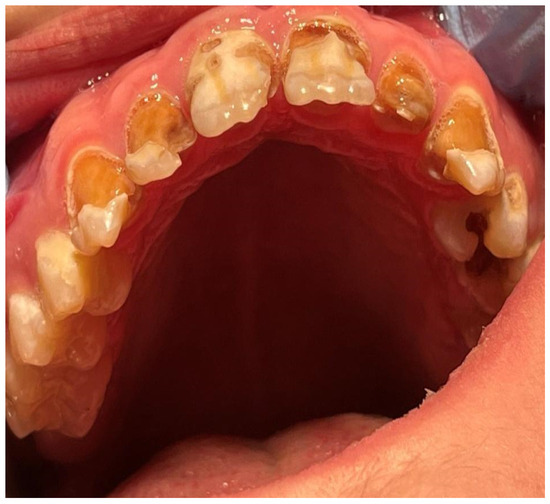

Use of Computer Digital Techniques and Modern Materials in Dental Technology in Restoration: A Caries-Damaged Smile in a Teenage Patient

2. Case Report